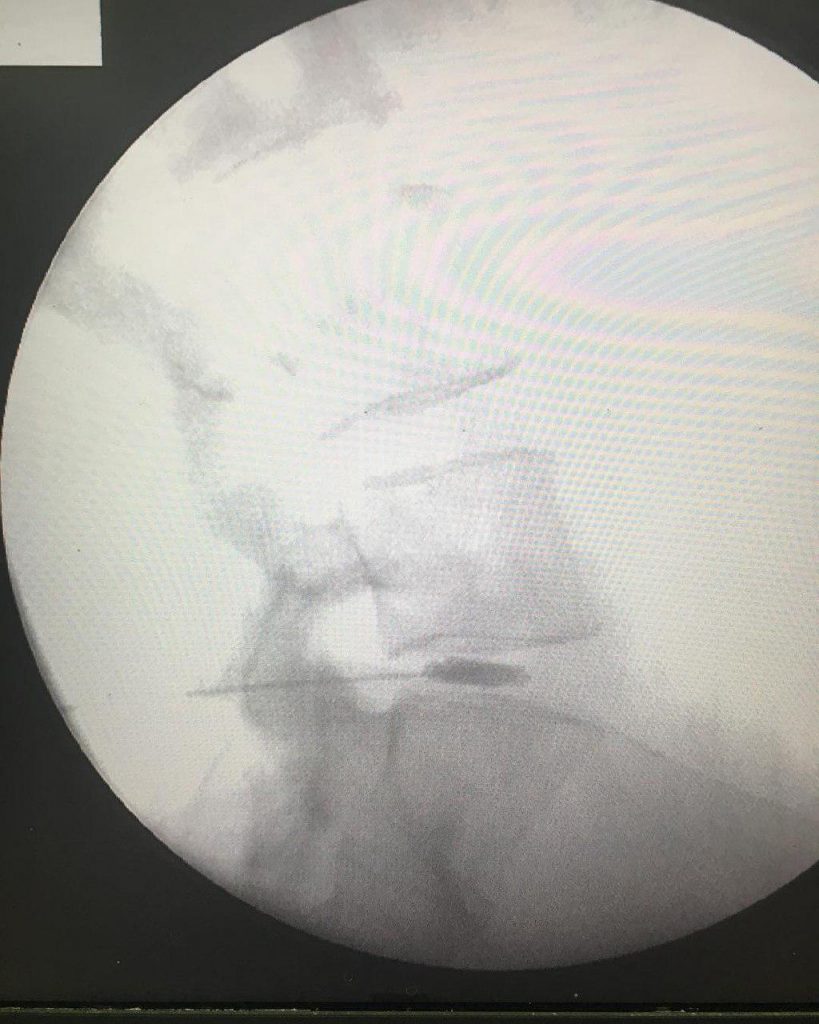

-لیزر(جراحی بسته) دیسک کمری

استفاده از روشهایی مانند تزریقات تخصصی (مانند اپیدورال، بلوک عصبی)، طب سوزنی، فیزیوتراپی، تحریک الکتریکی عصب و روشهای کم تهاجمی جراحی.